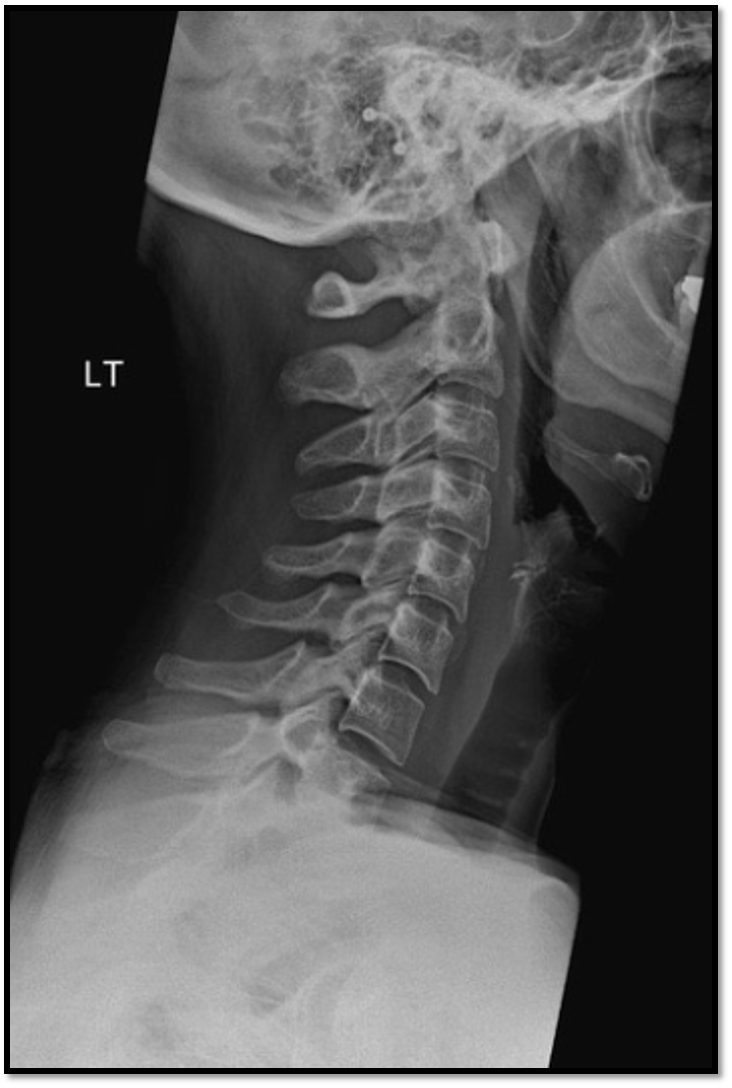

• rotation issue: posterior borders arent aligned

• tilt issues: double lines at zygo joints

• need to do swimmers: cant see C7 and T1